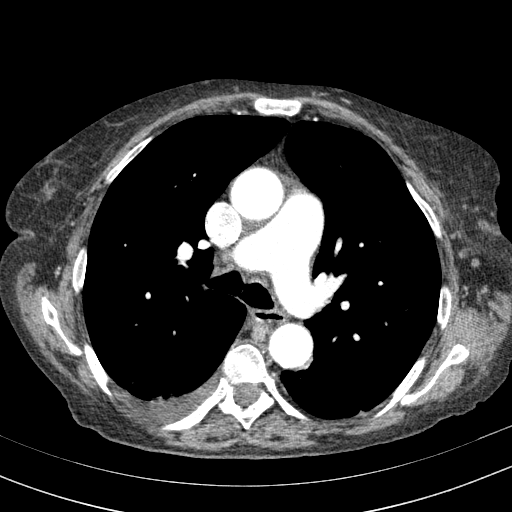

Generated VENOUS CT scan (A→B translation)

Full window (WL 1023.5, WW 4095 β†’ Low βˆ’1024, High +3071)

Actual HU range: [-1024.0, 847.3]